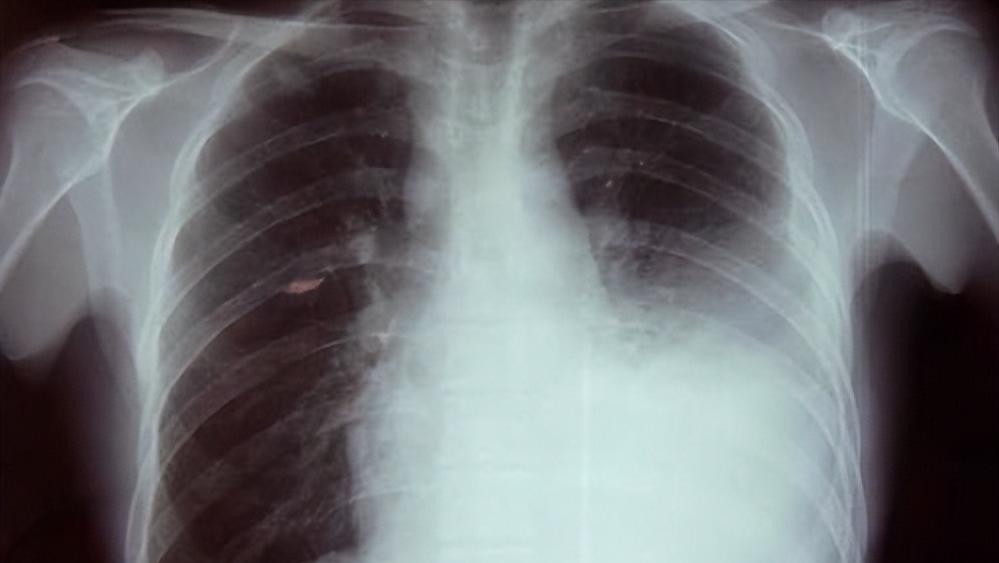

经过漫长的等待后,结果终于出来了,肿瘤标记物正常,血常规显示白细胞稍微有所升高,但是血沉加快。而胸片显示小王的肺部大片高密度阴影,而且胸膈角变钝。小王得的确实是胸膜炎。